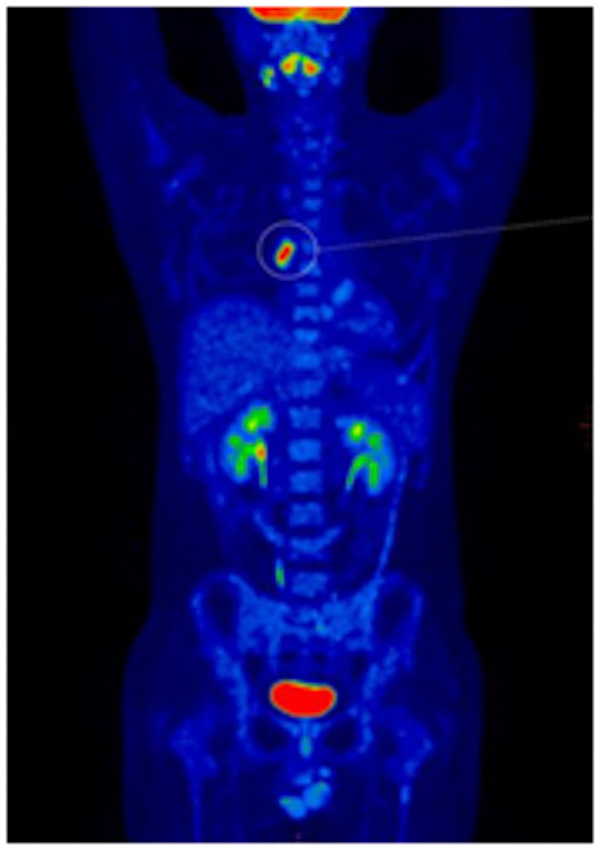

患者頸部及腋窩的淋巴結(jié)是不是都是淋巴結(jié)浸潤?全身還有哪些地方受淋巴瘤的浸潤?為了進(jìn)一步得到準(zhǔn)確的結(jié)果,患者到核醫(yī)學(xué)科進(jìn)行PET-CT檢查,淋巴瘤病灶立即無所遁形!

▲患者全身MIP圖:全身多發(fā)淋巴結(jié)淋巴瘤浸潤(A)

PET-CT能夠一次獲得全身檢查圖像,除了頸部及腋窩,其他部位的病灶也能一覽無余,患者的臨床分期發(fā)生了改變,為臨床醫(yī)生選擇治療方案提供了極大的幫助。